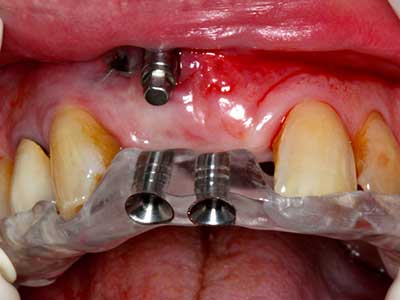

Fig. 13: En este paciente de 52 años con una anchura del hueso residual del maxilar inferior de 4 mm, hay que asegurarse de que exista refrigeración por agua adecuada durante la partición del hueso.

Fig. 14: Incorporación de cuatro implantes RSX cónicos (Bego Implant Systems, Bremen).